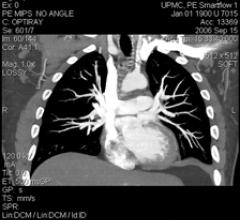

A broad array of contrast and injection management products for diagnostic imaging in radiology are provided with the EmpowerCTA Contrast Injector by ACIST Medical Systems Inc. The system is integrated with the IRiSCT Data Management System, provides a new level of integrative, informative and intuitive solutions to radiology suites around the world.